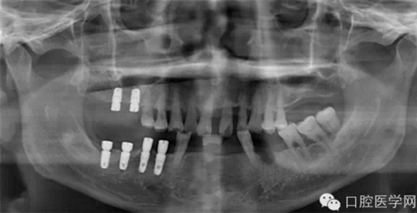

第六種,美國(guó)3I種植體

第七種 韓國(guó)美格真種植體

第八種,韓國(guó)登騰種植體